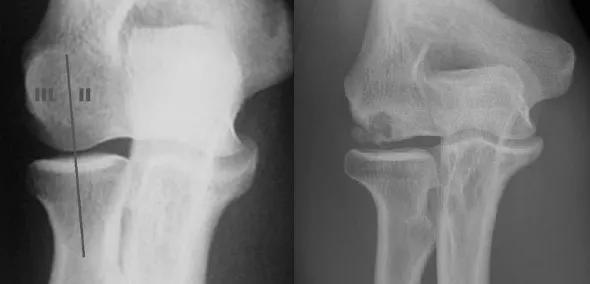

This modification is based on the location of the lesion on the capitellum, as determined on a 45-degree flexed, supinated view of the elbow (Figures 1 and 2). The capitellum is divided into two halves, defining medial (type II) and lateral (type III) lesions. Radiographic grade is assessed using the Minami classification.

Figure 1. (left) A 45-degree flexed, supinated anteroposterior X-ray view of an elbow with type II (medial) and type III (lateral) OCD lesions. Reprinted from Kolmodin and Saluan.2. Figure 2 (right). X-ray of an elbow with a type IIIb OCD lesion. Reprinted from Kolmodin and Saluan.